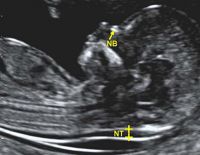

Đo độ mờ da gáy là gì và ý nghĩa khi thực hiện trong thai kỳ

Một trong những kiểm tra cần thiết trong thai kỳ mẹ cần thực hiện là đo độ mờ da gáy. Việc đánh giá thai nhi có nguy cơ bị bệnh Down hay không chính là nhờ vào phương pháp này. Tuy nhiên, tính chính xác...

Độ mờ da gáy bình thường là bao nhiêu, tại sao phải đo?

Độ mờ da gáy bình thường là bao nhiêu, tại sao bác sĩ phải đo độ mờ da gáy là những kiến thức cơ bản bạn phải nắm vững. Đây là một thông số quan trọng giúp bác sĩ xác định xem bé có khỏe...